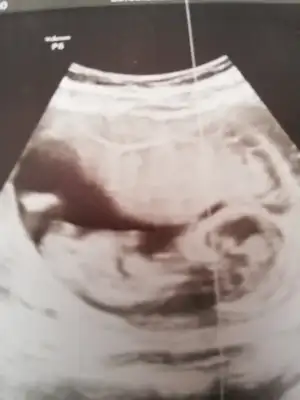

Ikra meyra Ikra meyra 13 haftalık gebelik canım doktor önce erkek dedi sonra kız da olabilir dedi yorumun var mı

Eklentiler

• IMG20210325190828.webp

IMG20210325190828.webp

26,5 KB · Görüntüleme: 87